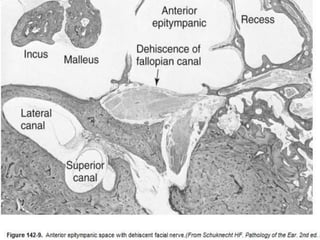

 Dehiscences of the mastoid portion of the

fallopian canal, even in the presence of mastoid

disease, are infrequent.

 This is in contradistinction to the tympanic

segment of the facial nerve, where congenital

and disease-mediated dehiscences are

common.

 The facial nerve in the floor of the

anterior epitympanic space can be

dehiscent, especially if extensive

cholesteatoma involves this region

(Fig.).